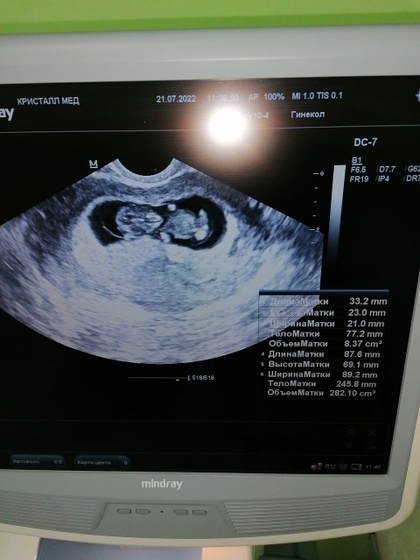

Узи 10,1 нед

Девочки, лежу значит я, смотрю телик и вдруг понимаю что я хочу на узи?️?Звоню в платную в 11:00, а мне говорят что есть местечко на 11:30.Собираюсь, еду.По узи все хорошо: малыш опережает на 2 дня(10,3 нед), сердечко бьется, шейка 35 мм???. Дали посмотреть по экрану: так куваркался малыш, такой славненький?. Мой зайка???!!! Сделала фото. Жду 1 скрининг теперь, 10.08